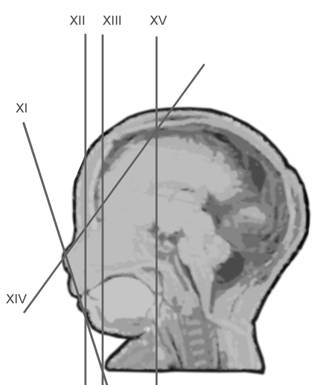

Planul XI - plan oblic ce indica nasul si mandibula, regiunea oronazala. Integritatea buzei superioare se confirma in special cand gura este deschisa.

Fig. nr. 165. Planul XI oblic coronal ce pune in evidenta narile si buzele.

Planul XII - plan coronal tangential, ideal pentru evidentierea pleoapelor si imaginea de "fat dormind

Fig. nr. 166. Planul XII coronal indica pleopele inchise ( sub linie )

Planul XIII - indica simultan orbitele si regiunea mandibulara, cristalinul apare ca un inel ecogenic in partea anterioara a orbitelor. Miscarile lente sau rapide ale ochilor pot fi cateodata evidentiate.

Planul XIV - plan oblic pentru orbite si nas.

Planul XV - planul longitudinal coronal la nivel de cavum septi pellucidi, evidentiaza cortex, corpus calosum, ventriculi laterali.